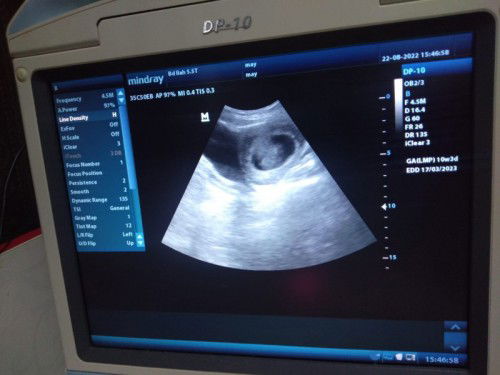

10 week 2 kantung janin

Kmrn sore aku usg bun kata bidan ada 2 kantung yg 1 udh ada janin yg 1 msh kosong kemungkinan kembar apa itu bnr bun

sama aku Bun, USG pertama 5w3d cuma 1 kantung, USG kedua 8w6d ada 2 kantung, 1 ada janin & detak jantungnya, 1 nya kosong Bun tp yg dicetak USG yg ada janinnya sja, kata dokter ini mau kembar gk jadi, tp bisa jd juga nanti ada janinnya, disuruh nunggu USG berikutnya Bun